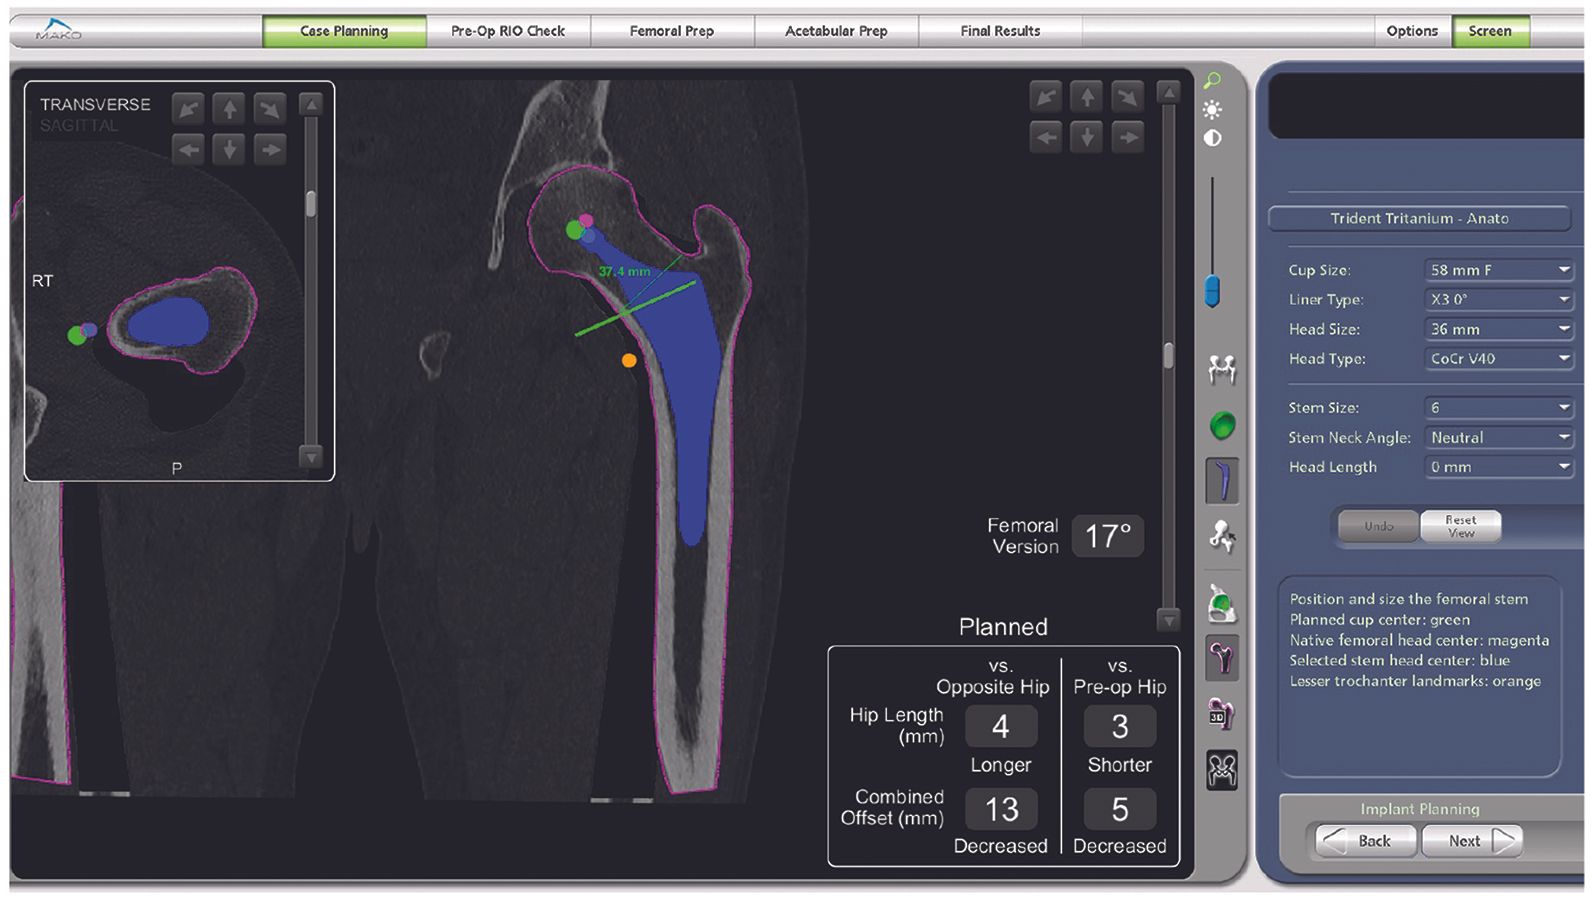

The robotic arm comes with software with the ability to plan implant placement using patient-specific anatomic markers and native acetabular geometry, centre of rotation, femoral version, offset and comparative length of the operated hip.

For a total hip arthroplasty (THA), the patient data are collected in advance using a preoperative CT scan with the ability to calibrate the field (knees can be included in the field in order to assess femoral version). Once the CT scan is complete, the specialist Segmentation Team creates a patient-specific virtual 3D model of the pelvis and femur. Using the surgeon’s preferences, the Segmentation Team will also create an initial pre-plan and select the CT landmarks.

One of the key stages prior to the procedure the surgeon’s approval of the plan proposed by the MPS (Mako Product Specialist) or engineer. The surgeon has complete flexibility, during the preoperative planning, to adjust various components of the plan based on the implant used, including:

- acetabular component orientation (Fig. 1),

- centre of rotation

- hip length

- cup overhang, especially anterior

- cemented or cementless, anatomic or straight, anteverted or neutral stem (Fig. 2)

- combined offset (Figs 2 & 3)

- combined anteversion, based on safe zone data,

- bone sparing i.e. minimization of reaming diameter by choosing a smaller cup, whilst respecting the other elements.

- leg length (Fig. 3).

These choices are unpredictable and, in all cases, will depend entirely on the surgeon’s preferences when validating the final plan (Fig. 4), although changes may still be made mid-procedure based on findings or constraints.